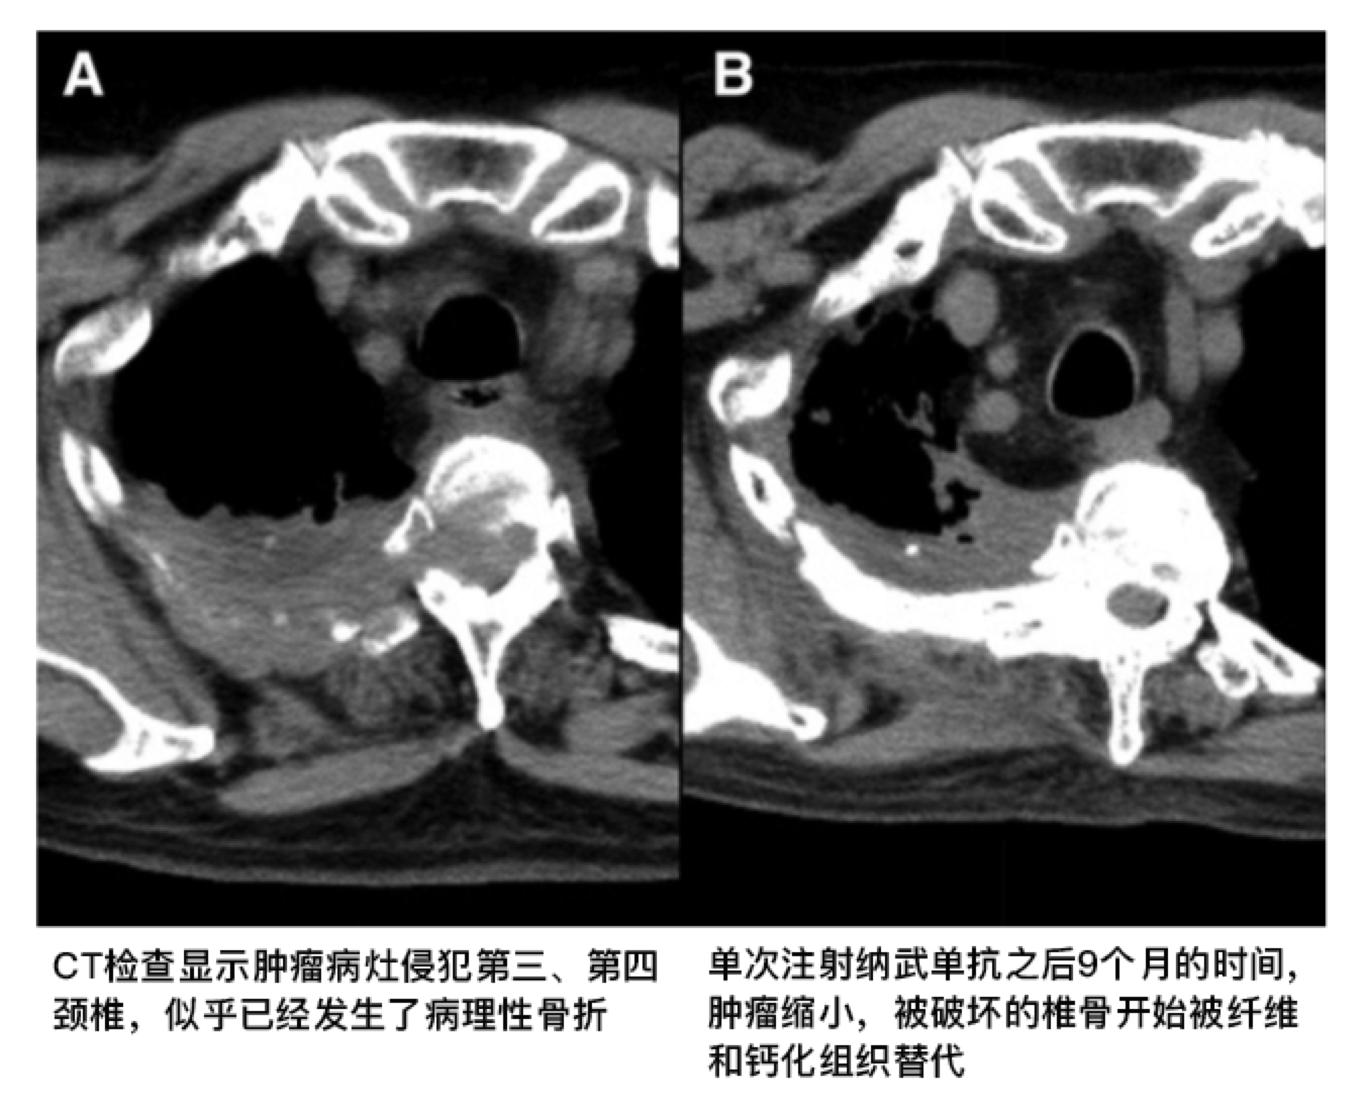

再次CT检查发现肝部转移灶逐渐萎缩,最后病灶完全消失,肿瘤原发灶也逐渐地缩小,之前被肿瘤破坏的椎体逐渐被纤维和钙化组织替代,PET-CT再次检查没有发现异常的肿瘤病灶。病人双侧下肢的麻痹消失了,也逐渐地停用了羟考酮和氧疗。

距离他单次注射PD-1纳武单抗已经过去17个月了,目前患者没有任何的症状,更为神奇的是使用Dako 22C3试剂盒去回顾性地检查之前穿刺活检的样本,发现PD-L1的表达是零,也就是完全阴性。